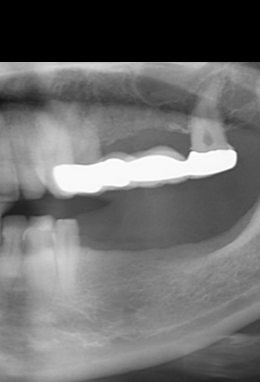

Placement of implants in positions 35i and 37i, with simultaneous placement of connective tissue graft.